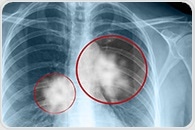

The latest respiratory diseases news from News Medical |

| | | New nuclear medicine tracer could improve diagnosis, treatment of non-small cell lung cancer Researchers have developed a new nuclear medicine tracer that could improve diagnosis and treatment of non-small cell lung cancer. Research published in the November issue of The Journal of Nuclear Medicine found that the new tracer, 99mTc-HYNIC-cMBP, produced clearer images in less time than currently used tracers and was more rapidly eliminated from the body, reducing radiation exposure. | |

| |  | | | Patients hospitalized for either asthma or chronic obstructive pulmonary disease have a higher risk of being readmitted for a hospital stay within 30 days of release if they also suffer from chronic rhinitis, according to a trio of researchers at the University of Cincinnati. | | | | | The largest-ever genetic study of people with moderate-to-severe asthma has revealed new insights into the underlying causes of the disease which could help improve its diagnosis and treatment. | | | | | A 'rule book' to guide precision combination immunotherapies and to speed up the development of new lung cancer treatments will be created as part of a collaboration between Cancer Research UK, the Francis Crick Institute and Bristol-Myers Squibb, announced today (Friday). | | | | | Scientists at the UCLA Jonsson Comprehensive Cancer Center have identified sodium glucose transporter 2, or SGLT2, as a mechanism that lung cancer cells can utilize to obtain glucose, which is key to their survival and promotes tumor growth. | | | | | Epigenetic therapies -- targeting enzymes that alter what genes are turned on or off in a cell -- are of growing interest in the cancer field as a way of making a cancer less aggressive or less malignant. | | | | | The World Health Organization estimates 387,913 Europeans will die of lung cancer in 2018. The preliminary findings from a new study by the Economist Intelligence Unit comparing 13 countries show that governments across Europe are responding in very different ways to the disease. | |